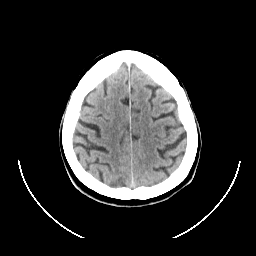

CT Study #1 -- Slice #23